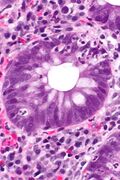

Additional images

Crypt abscess. H&E stain.